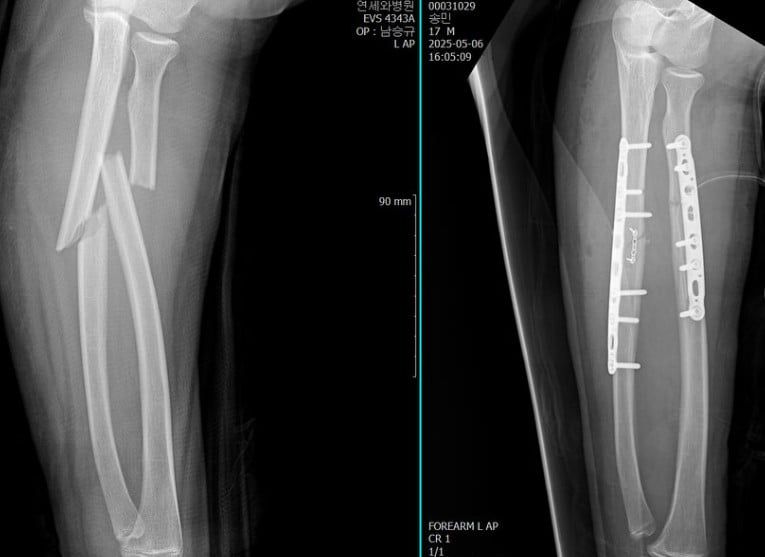

오윤아는 지난 14일 자신의 인스타그램에 "아 ... 저번주 ㅠㅠ 저희 민이가 덩치가 있어서 그런가 또 팔이 부러졌어요..."라며 아들의 부상 상황을 전했다.

이어 "너무 막막하고 ... 어째야할지 몰라서 민이를 잘 알고 계신 원장님이 계신 병원으로 연락했어요... 인천이라 멀긴했지만 또다른 선생님께서 너무 잘 수술도 해주시고 뒤에 상처 꼬메는것과 소독까지 다 꼼꼼하게 처리해주셔서 ㅠㅠ 너무 잘 치료받고 회복하고있어요"라는 글과 함께 여러 장의 사진들을 게재했다.

공개된 사진들 속에는 오윤아의 아들의 팔이 너무나 선명하게 부러진 모습. 이에 아들은 수술을 받았고, 그 결과 깔끔해진 뼈대를 보였다. 이후 아들은 아이스크림을 먹는 등 환한 미소를 보이기도 했다.